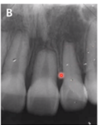

this radiograph is an example of what type of resorption?

Orthodontic pressure root resorption